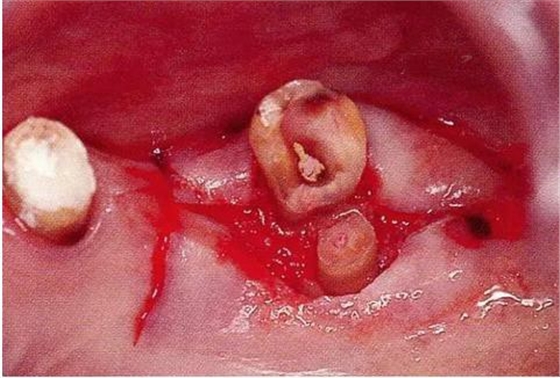

▼圖18-3

圖18-3 在其他醫(yī)院進(jìn)行了的修復(fù)處理。拔除了第一磨牙遠(yuǎn)中根的病例。近中根遠(yuǎn)中面殘留著一部分的邊緣。在這種部位很容易滯留牙垢,菌斑的控制會(huì)也很困難。